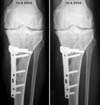

Freitag, 12. August 2005, 09.45 Uhr: Röntgenbilder

Röntbenbild 11.8.2005 - klicken für grösseer FassungGute Neuigkeiten: Endlich von den Schläuchen und diesem sehr praktischen Infusionsständer befreit! Das erste Mal wieder in seitlicher Lage geschlafen! Welch immensen Geschenke - das erhöht die Lebensqualität schon mal beträchtlich, auch wenn ich noch immer recht schläfrig bin und schwere Augenlider habe. Vorhin schlich ich mich nach dem Röntgen zum ersten Mal an die Sonne raus. Blick auf die Berner Alpen und die Gantrischkette im Morgenlicht... Tut das gut! - Ach ja, Röntgen: Vorerst gibts nur Handyfotos, aber da sieht man schon, dass recht herumgesägt wurde... uff. - Prof. Stäubli war soeben da und ist weiterhin zufrieden. Jetzt gehts bald in die Physio. Das Morgenpanorama ist wieder einmal traumhaft (klicken für grössere Fassung).

15. August, 23 Uhr: Eine Woche danach

Lucia, Ursina und Salome ("in diesem Spital riechts gar nicht nach Spital, eher nach Skilager") versüssten den Abend - und ich sitze im Aufenthaltsraum, sodass mein neuen Zimmernachbar (87 und frisch operiert) in Ruhe schlafen kann. Ist auch ein guter Test für daheim: Wieder möglichst mobil und erfindungsreich, was Transportmöglichkeiten angeht. Ich habe inzwischen bessere Fotos der Röntgenbilder erstellt und ein paar Spielereien gemacht - bitte auf Bilder oder Links klicken für grössere Fassungen:

Auswahl von unbearbeiteten Röntgenbildern in guter Auflösung

Seitliche Bilder, Serie 2001-2005

Vergleich der Tibia vor und nach der Osteotomie, mit Animation - hier ist schön sichtbar, wie die Gelenksachse gemäss dem Plan vom Mai korrigiert wurde

Die aktuellen Röntgenbilder (bitte klicken für grössere Fassungen):

Mal was Neues - Übersicht beide Beine inkl. Becken

Dasselbe Bild wie oben, Ausschnitt Knie

Vergleich 15. August 2005 und 19. September 2005 von vorne

Vergleich 15. August 2005 und 19. September 2005 von der Seite